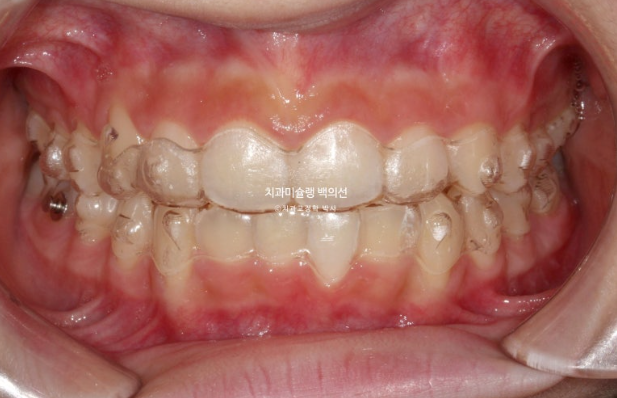

2024.02~2025.04

유지장치까지 들어간 모습입니다.

총 치료기간은 1년 2개월, 재제작은 1회 했습니다.

중심선은 정확하게 맞으며 과개교합이 잘 해소되었습니다.

어금니 교합은 물샐틈 없는 1급입니다.